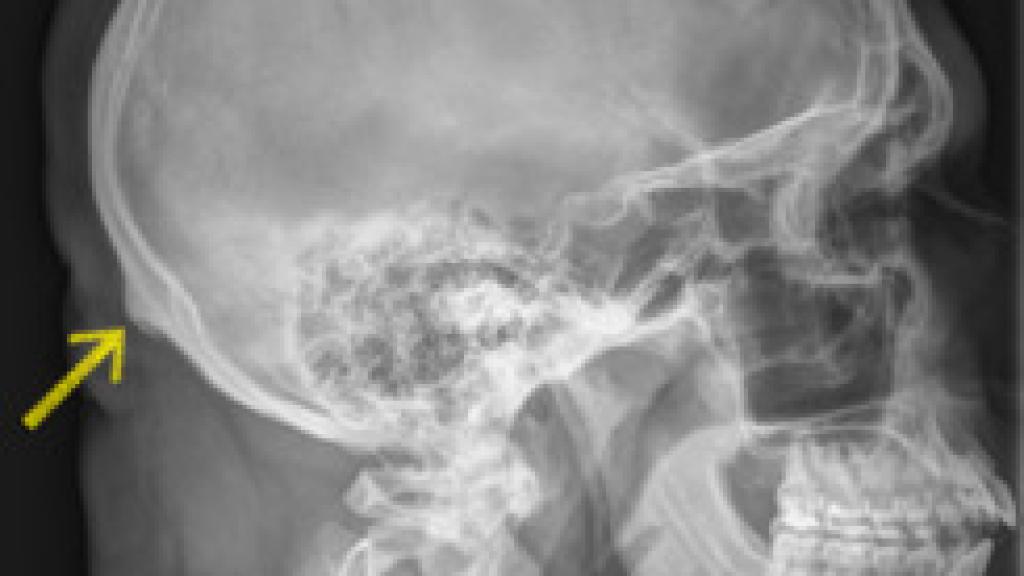

La semana pasada irrumpía en las redes sociales una noticia: por culpa de nuestra relación viciosa con el teléfono móvil y la inclinación de la cabeza que forzamos para mirar la pantalla, el ser humano está desarrollando un "cuerno" en la parte posterior del cráneo. Estas noticias virales invitaban a los lectores a palparse el área donde se encontraba la protuberancia en cuestión. Justo en el lugar en el que la columna vertebral se inserta en el cráneo.

Cuando llevamos nuestras manos hacia esta región, podemos comprobar que es cierto que existe un pequeño saliente. Sin embargo, para nada es novedoso. Se trata de la protuberancia occipital externa, un accidente geográfico de nuestra anatomía craneal bien conocido por los científicos. Se trata del punto en el que se inserta parte de los músculos de la espalda, el ligamento nucal y el trapecio, en el cráneo.

En el año 2016, David Shahar, un investigador de la Universidad de Sunshine Coast,  estudió junto a un equipo de quiroprácticos una serie de radiografías de varios pacientes entre los 18 y los 86 años de edad. Destacaron que quienes tenían entre 18 y 30 años mostraron una protuberancia mayor. Los científicos lo asociaron rápidamente al uso de móviles y de tablets.

Según esta teoría, cuando inclinamos hacia delante la cabeza, que tiene un peso medio de 4,5 kilogramos, los músculos que conectan la espalda a la cabeza se tensan. La protuberancia del cráneo generaría nuevas capas de tejido óseo con el objetivo de resistir la tensión y, de esta manera, aumentaría de tamaño. Con estos datos, muchas webs hicieron circular el rumor de que se trataba de un paso más en la evolución del ser humano.

La evolución de una especie no se puede observar en la vida de un individuo, sino a través de varias generaciones. Además, Maldita Ciencia ha explicado que la muestra del estudio es muy reducida para explicar el origen del engrosamiento de la protuberancia. Según pudo saber la página web, el estudio contó con 218 sujetos, únicamente. El tamaño de estas protuberancias tampoco les pareció reseñable: entre 10 y 30 milímetros.